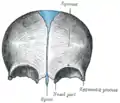

额骨内面(在顶部以蓝色显示)。

额骨。下面。